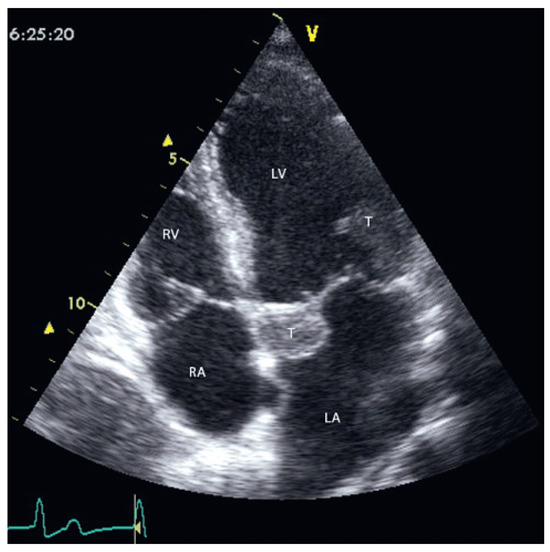

Fallbericht